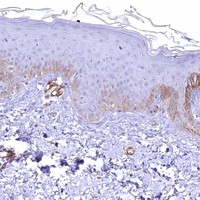

Enhanced - Orthogonal

Antibody staining mainly consistent with RNA expression data across 44 tissues.

HIGH EXPRESSION

Smooth muscle

RNA expression: 235.4 nTPM

LOW EXPRESSION

Skin 1

RNA expression: 17.3 nTPM